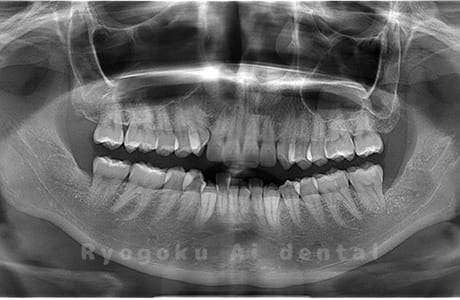

真っ直ぐ生えている親知らず

親知らずが真っ直ぐ生えているタイプです。

このタイプは真っ直ぐ生えていて咬み合わせに問題がなければ、抜歯しないケースもあります。ただし、虫歯になっていたり、痛みがあったり、咬み合わせが悪かったりすると抜歯をおすすめします。